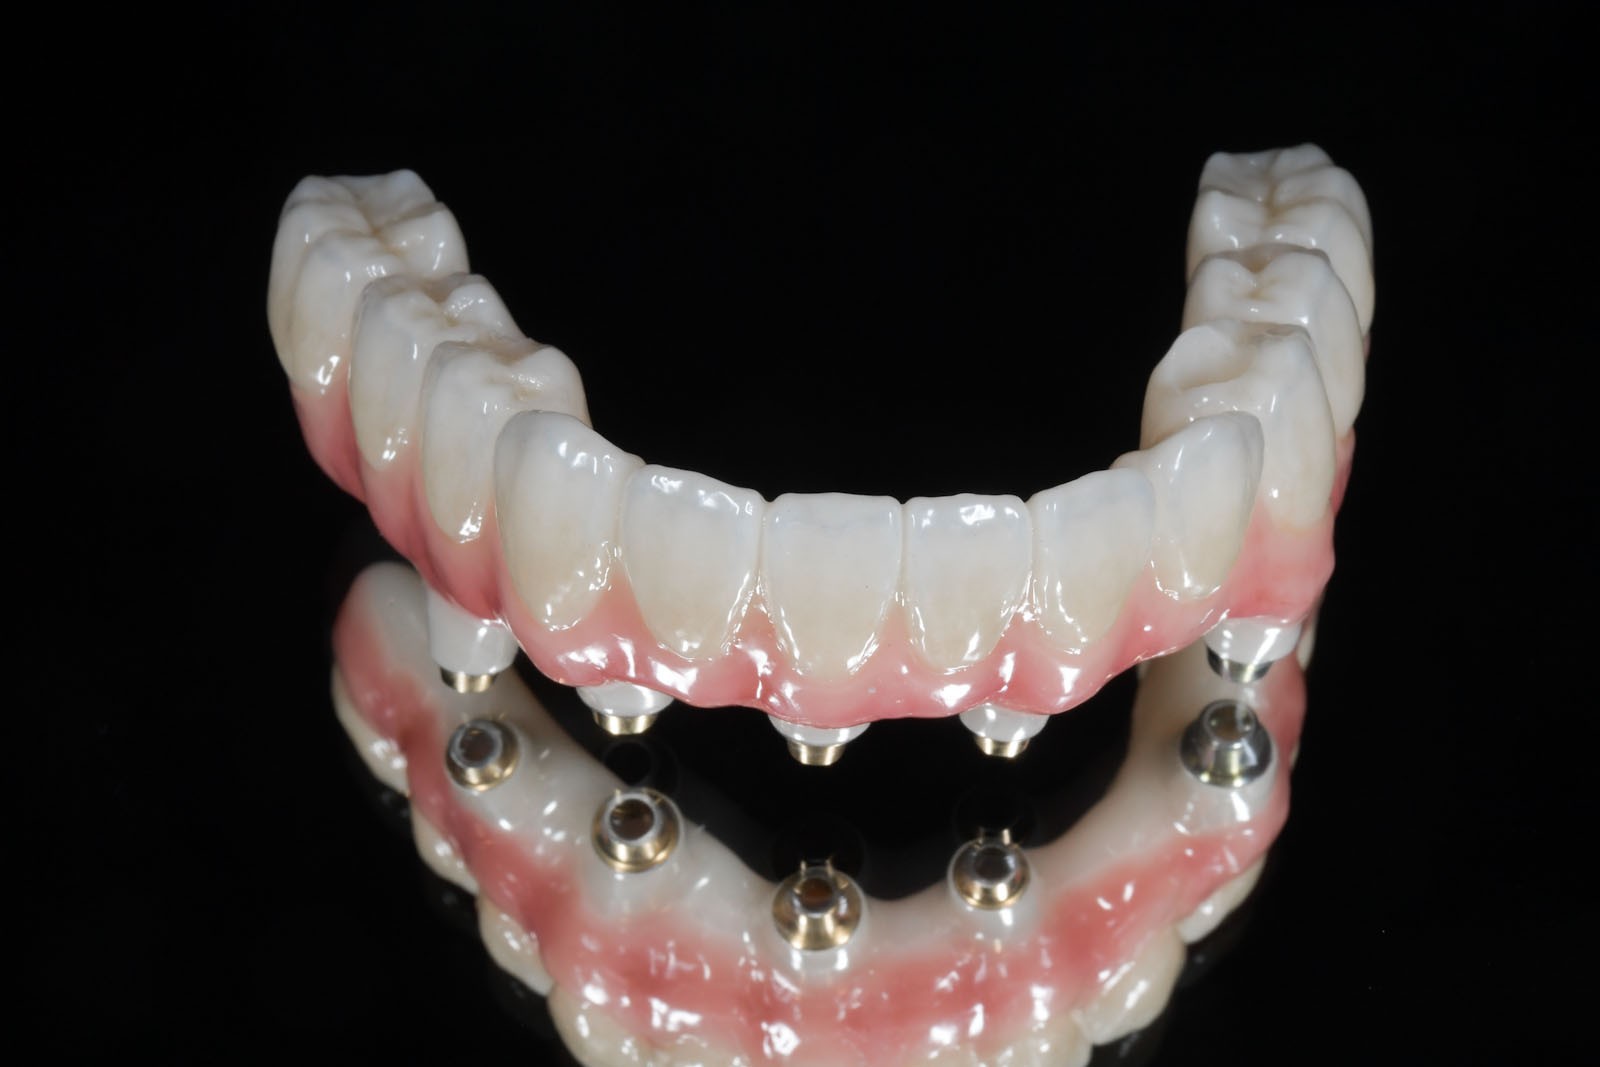

Uzupełnienia stałe w sposób permanentny, lecz nie rozłączny montowane są na zębach lub implantach w jamie ustnej pacjenta. Do stałych uzupełnień zaliczamy wkłady koronowo-korzeniowe, wkłady koronowe, licówki, korony i mosty oraz uzupełnienia stałe oparte na wszczepach śródkostnych.

Korony i mosty wykonane są na podbudowie metalowej, z tlenku cyrkonu lub ceramiki.

Współczesna protetyka stomatologiczna uwzględnia zastosowanie nowoczesnych materiałów. Zwykle bazą dla zaawansowanych technologicznie stałych prac protetycznych jest stop metalu, w tym tytanu, oraz tlenek cyrkonu. Najbardziej wymagające, jeśli chodzi o obróbkę laboratoryjną, są prace tworzone na bazie podbudowy z tlenku cyrkonu. Trudności, jakie stwarzają, rekompensowane są zwykle przez ostateczny efekt na etapie gotowych koron i mostów. Technologia służy wykonywaniu stałych prac protetycznych zarówno na zębach własnych pacjenta, jak i na implantach.

Komfortową alternatywą dla mostu jest rehabilitacja implanto-protetyczna, zarówno w przypadku braku pojedynczego, jak i większej liczby zębów. Implantacja wskazana jest w szczególności, gdy zęby sąsiadujące z luką są zdrowe, nie leczone kanałowo, a podłoże kostne spełnia warunki dla implantacji. Pozwala to uniknąć szlifowania zębów filarowych stojących obok luki, a przyszła konstrukcja protetyczna najczęściej nie uwzględnia przęsła mostu, które może sprawiać trudności w utrzymaniu higieny jamy ustnej. Korony i mosty wsparte na implantach przenoszą siły powstające w procesie żucia przez osie implantów wszczepionych w kość. Tworzy to układ działania sił najbardziej zbliżony do fizjologicznych warunków jamy ustnej z uzębieniem. Jest on optymalny dla zdrowia i zachowania tkanki kostnej. W ten sposób przenoszona siła powoduje wzmocnienie kości, nie zaś jej resorpcję, czyli zanik.

W związku z ich użytkowaniem skala komfortu dla pacjenta zależy od tego, czy są to ruchome protezy Overdenture oparte jedynie na implantach, które poprawiają stabilizację protez zębowych, czy też na stałe mocowane na wszczepach mosty. W ślad za wyborem rodzaju mocowania protez idzie jakość odbudowy protetycznej. Protezy Overdenture są wykonane z materiału kompozytowego lub akrylu, natomiast mosty są wykonane z ceramiki.